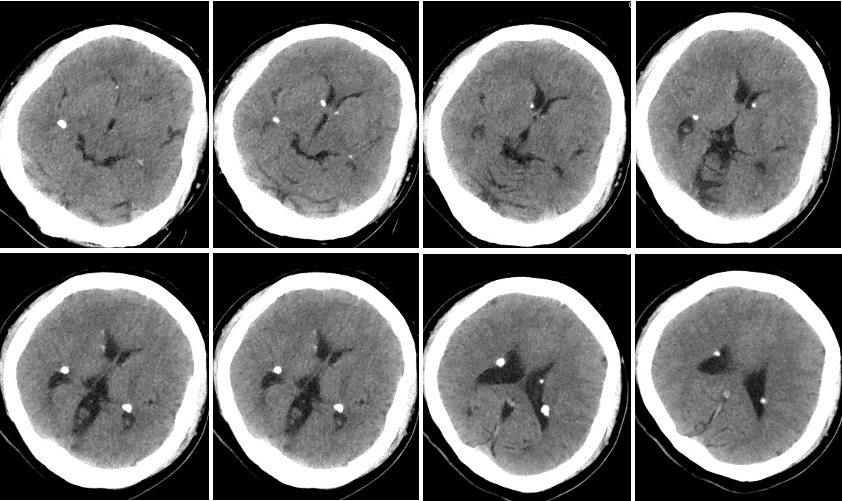

刘x,被人发现意识不清约2.5小时

一、病例特点患者男性,75y,急性起病;临床表现为意识不清;既往有高血压及冠状动脉粥样硬化性心脏病病史,院外用药情况不详; 查体:T 38.4℃,P 89次/分,R 18次/分,BP 160/86mmHg,神志不清,浅昏迷状态,认知不能评价。肢体肌力检查不配合,左侧肢体肌张力较右侧偏低。双侧巴宾斯基征阳性,NIHSS评分:18分,格拉斯哥评分:5分,mRs评分:5分,洼田饮水试验:无法完成。辅助检查:ECG:窦性心律,下壁心肌梗死(时期未定),逆钟向转位,V4~V6导联T波低平双向。二、神经影像胸部CT(2025-7-30 本院):双肺见条片状高密度影,右侧胸腔内可见包裹性液体密度影。双侧胸膜增厚,部分钙化。头CT:右侧侧脑室见片状高密度影,脑室内见多发不规则高密度影。双侧大脑半球脑沟内高密度影,额部颅板下见积气影。小脑、右顶叶、双侧额叶、放射冠区、基底节区见半片状低密度影,局部近液体密度影;脑室及脑池系统扩张。双侧脑沟裂增宽、加深,中线结构居中。病情转归 1、入院后联系神经外科,鉴于出血量大,征得家属同意后行颅内出血置管引流术,间断引流血性液体,复查CT提示出血减轻,意识也曾一度清醒,示意肢体 可简单活动; 2、8月3日患者意识成昏迷状态,复查CT提示再次出血,急诊ICU告知病情加重预后不良,家属经商议后放弃治疗。三、初步诊断意识障碍(出血性脑血管病疾病) {x} PS:复盘患者CT情况,颅内出血大部分集中在右侧颞叶,累及中脑环池,且破入侧脑室,考虑患者存在后交通动脉瘤可能性大。